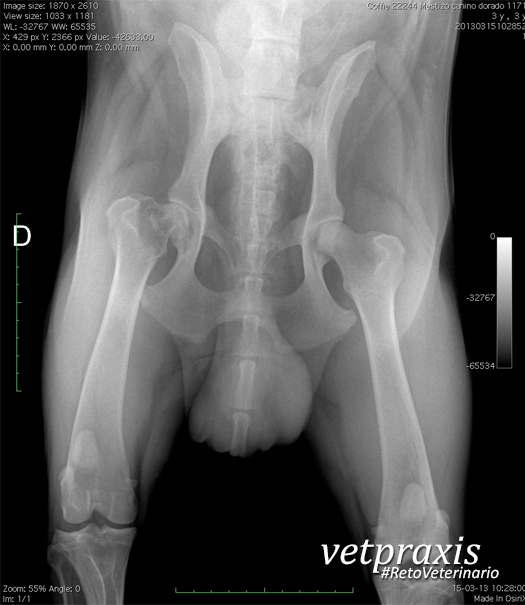

Se recibe un paciente con orden radiográfica para proyección V-D de pelvis por antecedentes de claudicación. Es un perro mestizo de Labrador Retriever / Ovejero Alemán de 3 años de edad y 38 kilos. Luego de observar la proyección disponible, su radiodiagnóstico corresponde a :

a) Displasia de cadera bilateral

b) Necrosis avascular de la cabeza femoral (Legg Perthes canino)

c) Proceso óseo agresivo de fémur proximal derecho.

d) Fractura de cuello de cabeza femoral derecho.

e) Fractura Salter Harris I de cuello de cabeza femoral derecho.